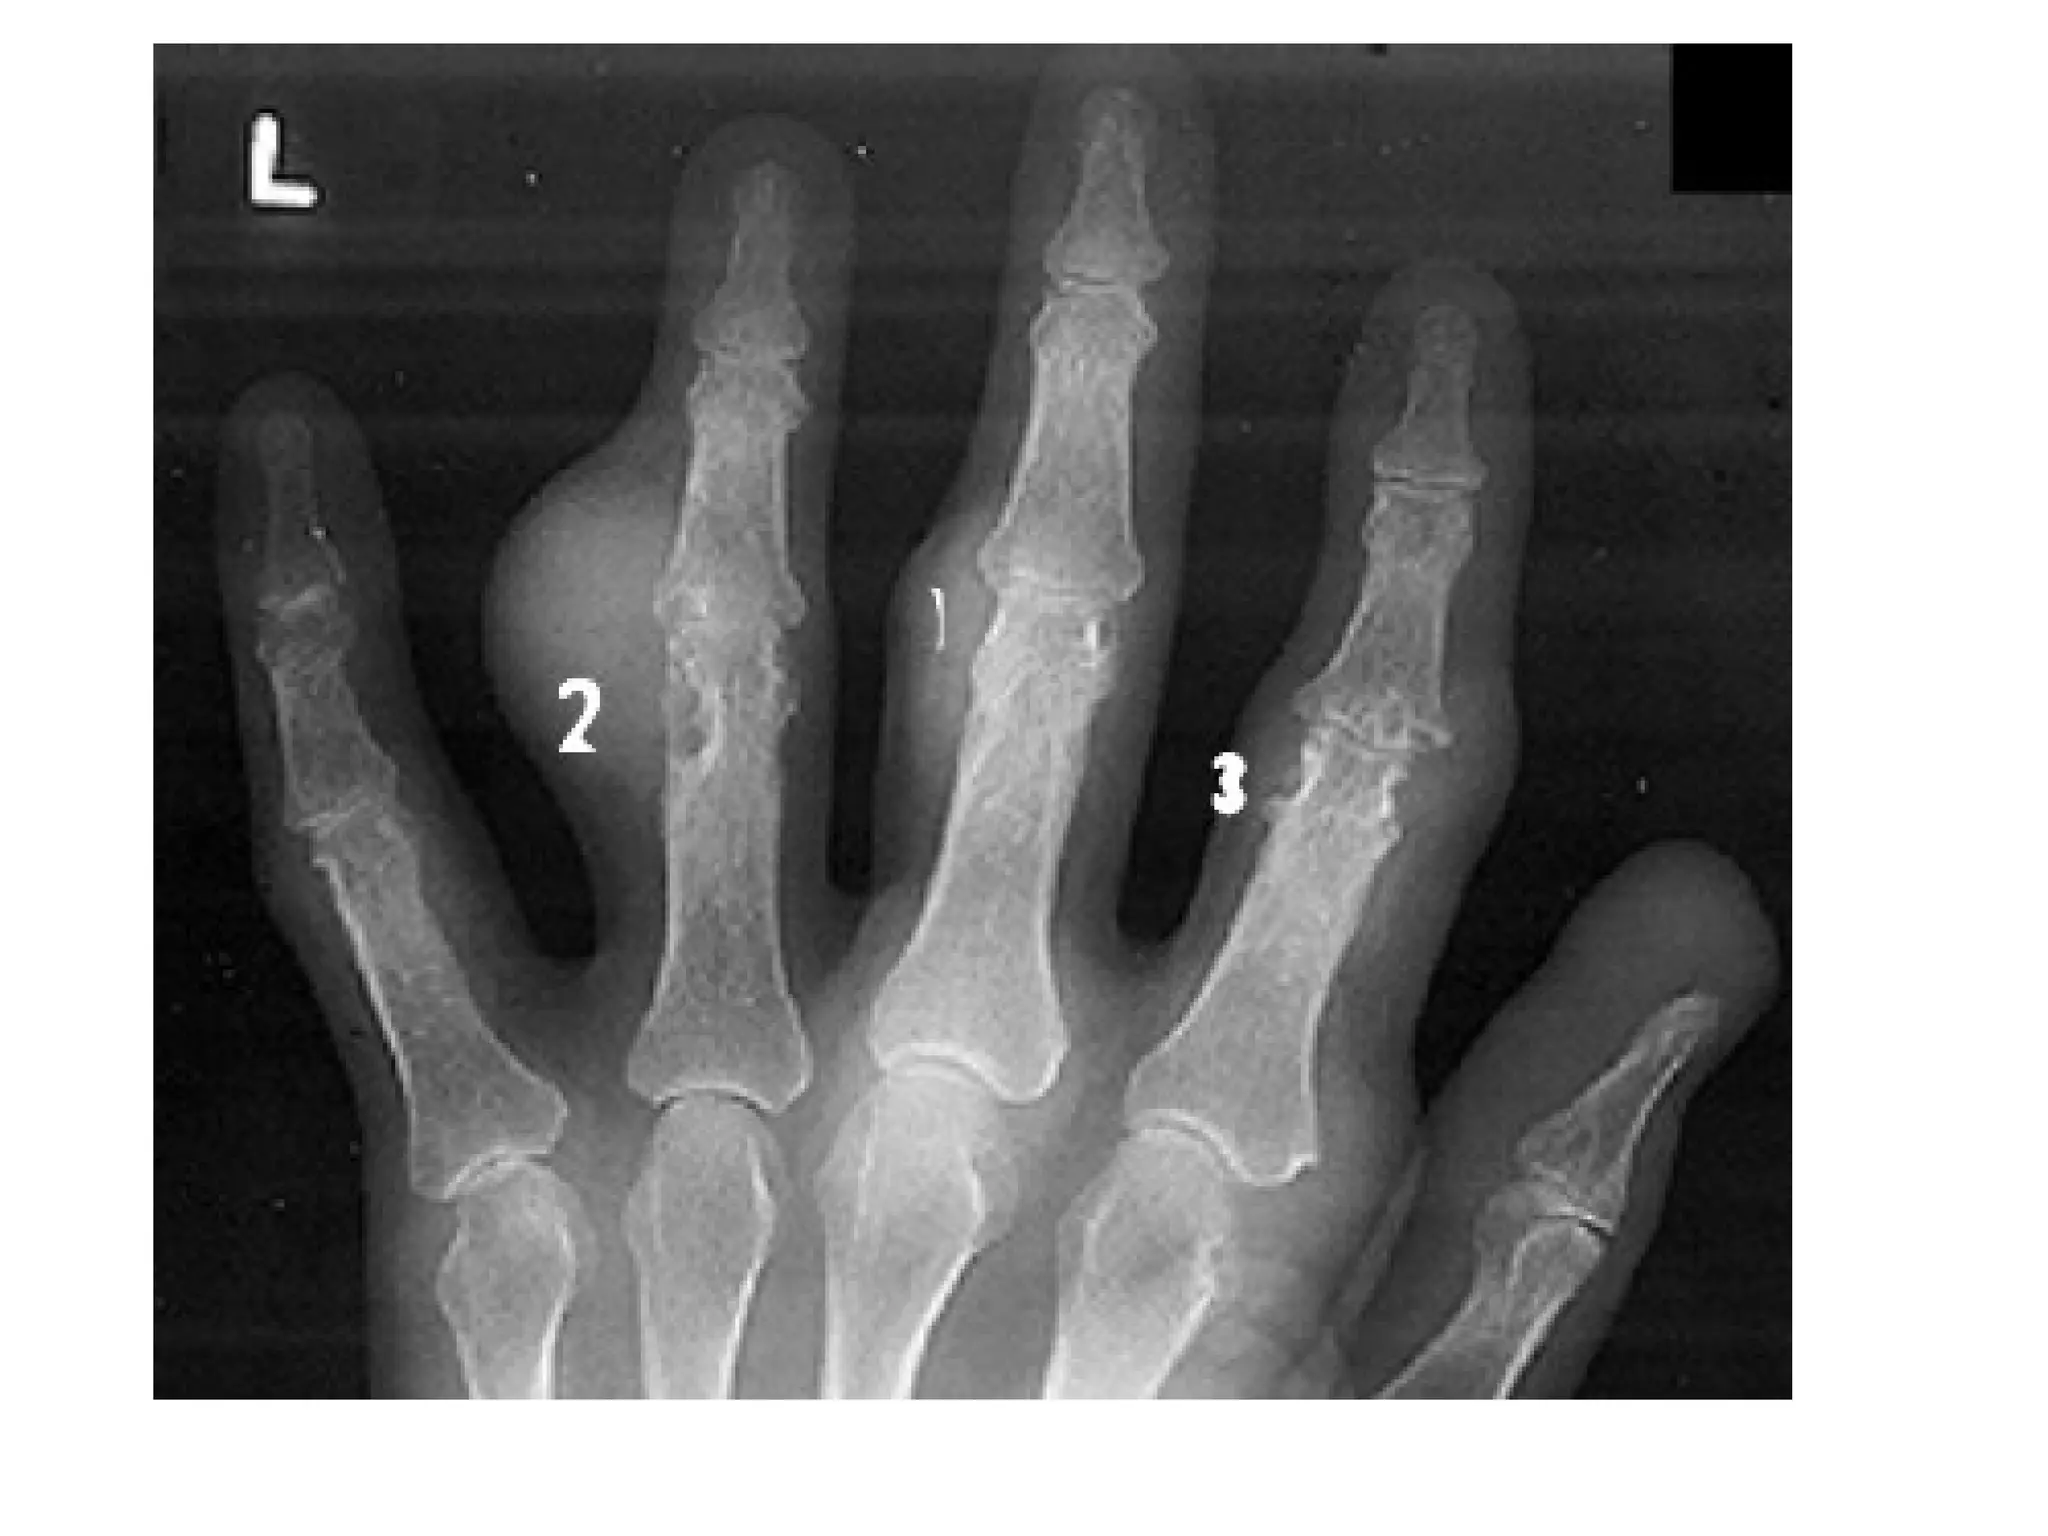

Tophaceous gouty arthritis , extensive bony erosions are noted

throughout the carpal bones , urate depositions may be present in

the periarticular areas